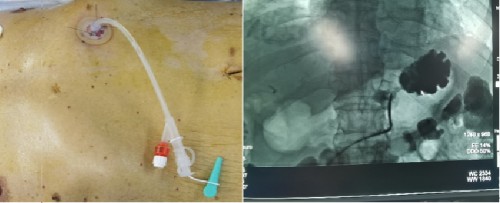

放射介入团队与肿瘤科符慧群教授充分讨论患者病情后决定给患者实施局麻下经皮胃造瘘手术。充分术前准备后,于4月27日上午,容鹏飞带领张声旺、骆雷、李万猛、胡幼青医护团队,采取经食管插管胃充气扩张萎缩的胃体,局麻下经前腹壁穿刺胃体并缝合固定于前腹壁、置入造瘘管,手术操作流畅连贯、一气呵成。患者在术中生命体征稳定、未诉任何不适。手术完成后97岁的老爷爷非常高兴,家属也表示由衷的感谢。

容鹏飞总结到,食管癌患者无法进食会导致患者一般情况持续变差。DSA引导下局部麻醉经皮穿刺胃造瘘手术操作时间短、创伤小,费用低,与其它方法比较并发症少,能够充分解决患者的营养问题,造瘘管维护方便、适当保护后患者可以淋浴,不影响生活质量。且经皮直接穿刺胃造瘘避免了内镜通过食管梗阻段造成的出血等并发症,一般情况差的患者也能耐受。